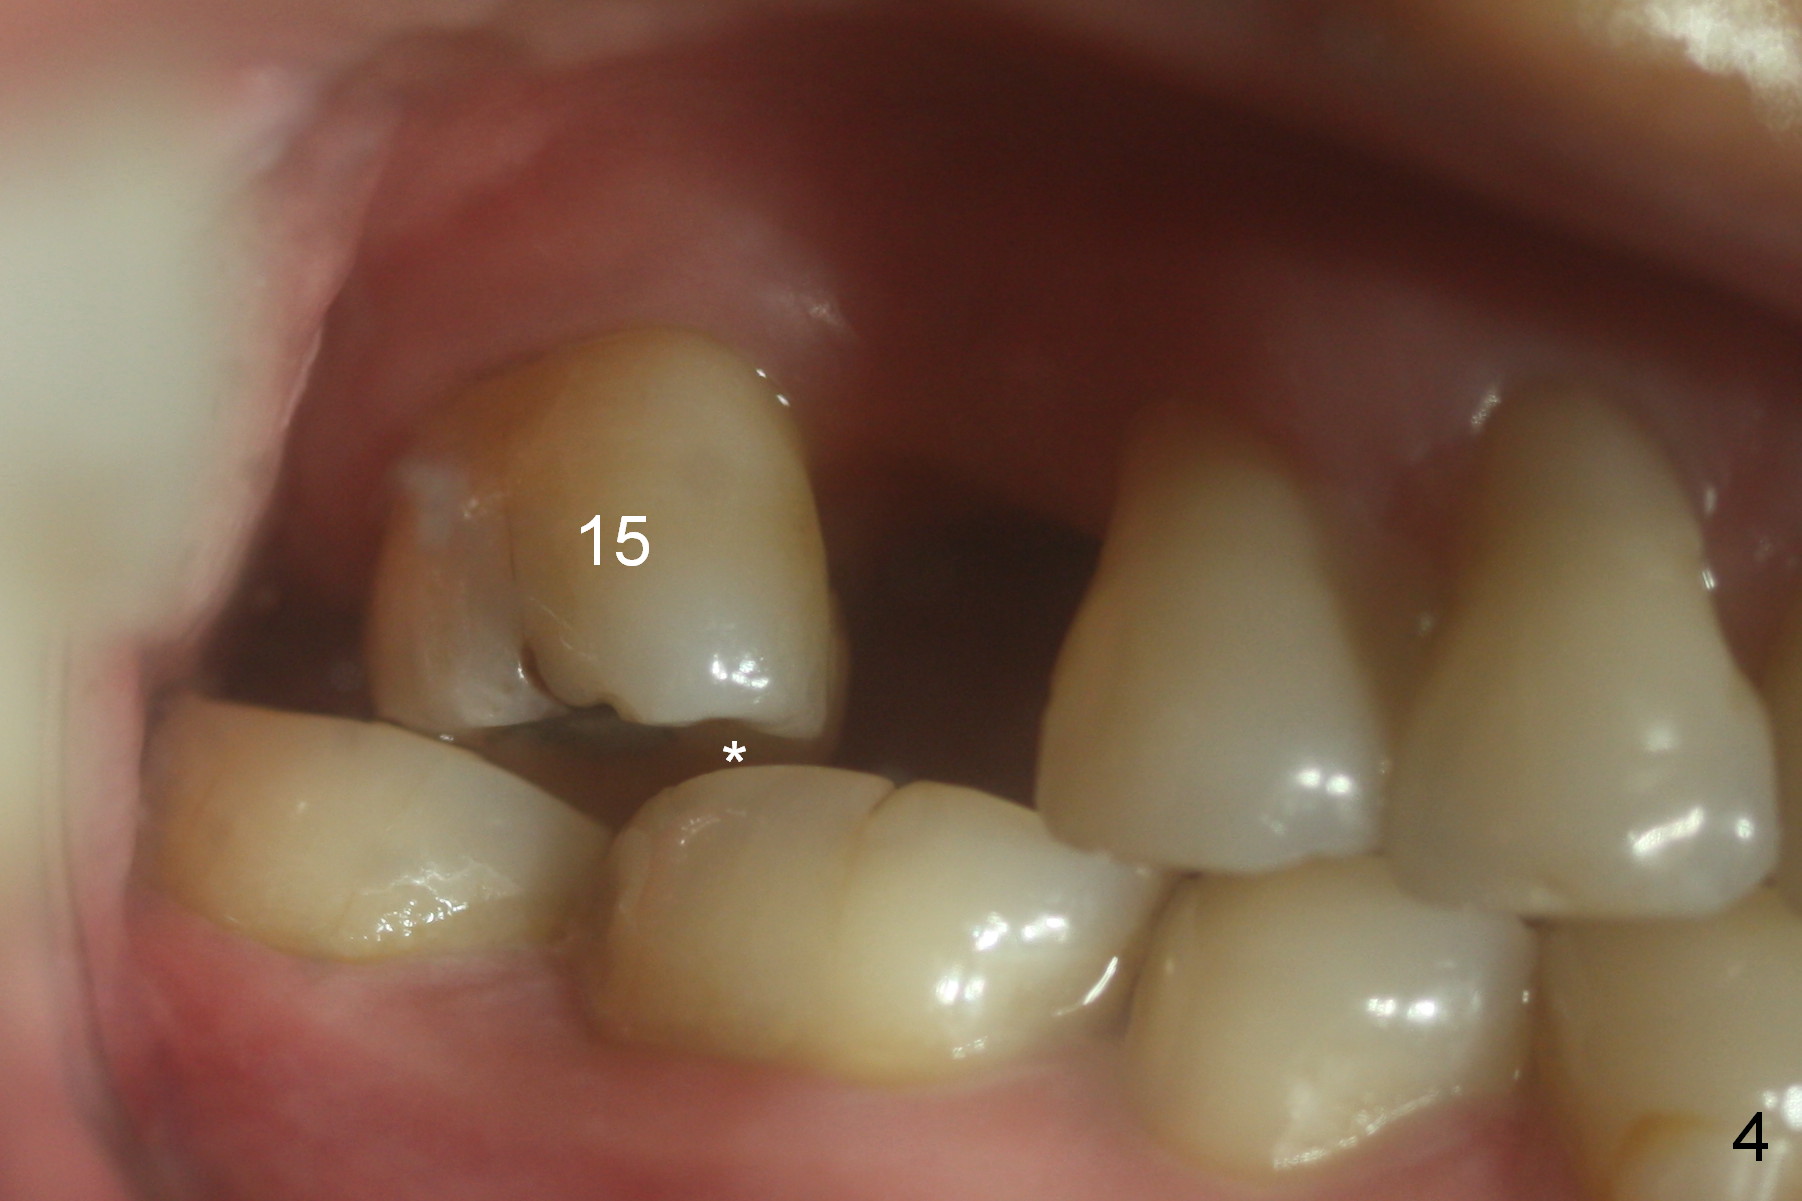

A 54-year-old woman had #14 extracted in China 1 year ago (Fig.1,5). The tooth #15 has undergone mesial shift and tilt (Fig.2,4, as compared to Fig.3). The edentulous space is too narrow for implant placement (Fig.6). It appears that traditional orthodontic appliance should be placed from UR6 to UL7 in addition to a mini-implant distal to UL7. Take Alginate impression before treatment. Since the implant at UR7 is placed apparently too deep, a band will be placed when it is initially osteointegrated (6-8 weeks postop). Fabricate a well-fit provisional with permanent cementation before banding. In fact, brackets and bands are placed between UR3 and UL7. In 6 months, the meisodistal space at #14 is enough to place an implant (Fig.7).